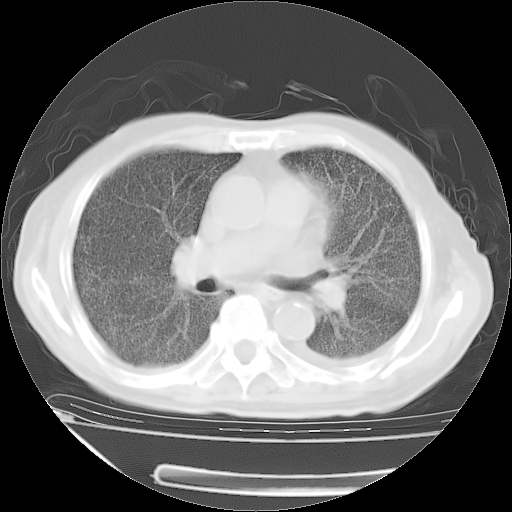

甲强龙80mg/日+抗结核治疗(异烟肼+利福霉素+乙胺丁醇)10天。复查肺部CT。

治疗10天肺部CT

今天带四次肺CT片到市医院,影像科4~5个主任都认为不考虑粟粒性肺结核。主要理由是在3月19日、4月2日、4月27日的CT片没有见到确切异常(肺结核)影像。影像科主任们建议找呼吸内科主任,呼吸内科主任认为首先考虑粟粒性肺结核。